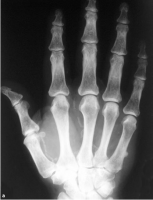

Calcificação das artérias pode ser devido a uma variedade de causas. Estes incluem o diabetes mellitus, hiperparatireoidismo, ateroma, aneurisma, intoxicação por vitamina D e síndrome de Werner. Esta alteração ocorre mais comumente nos membros inferiores. A calcificação arterial é facilmente detectado como calcificações lineares e curvilíneas nas paredes das artérias. Estas características são bem ilustradas na mão de um adulto com extensas calcificações arteriais da palma da mão e dedos nas figuras abaixo.